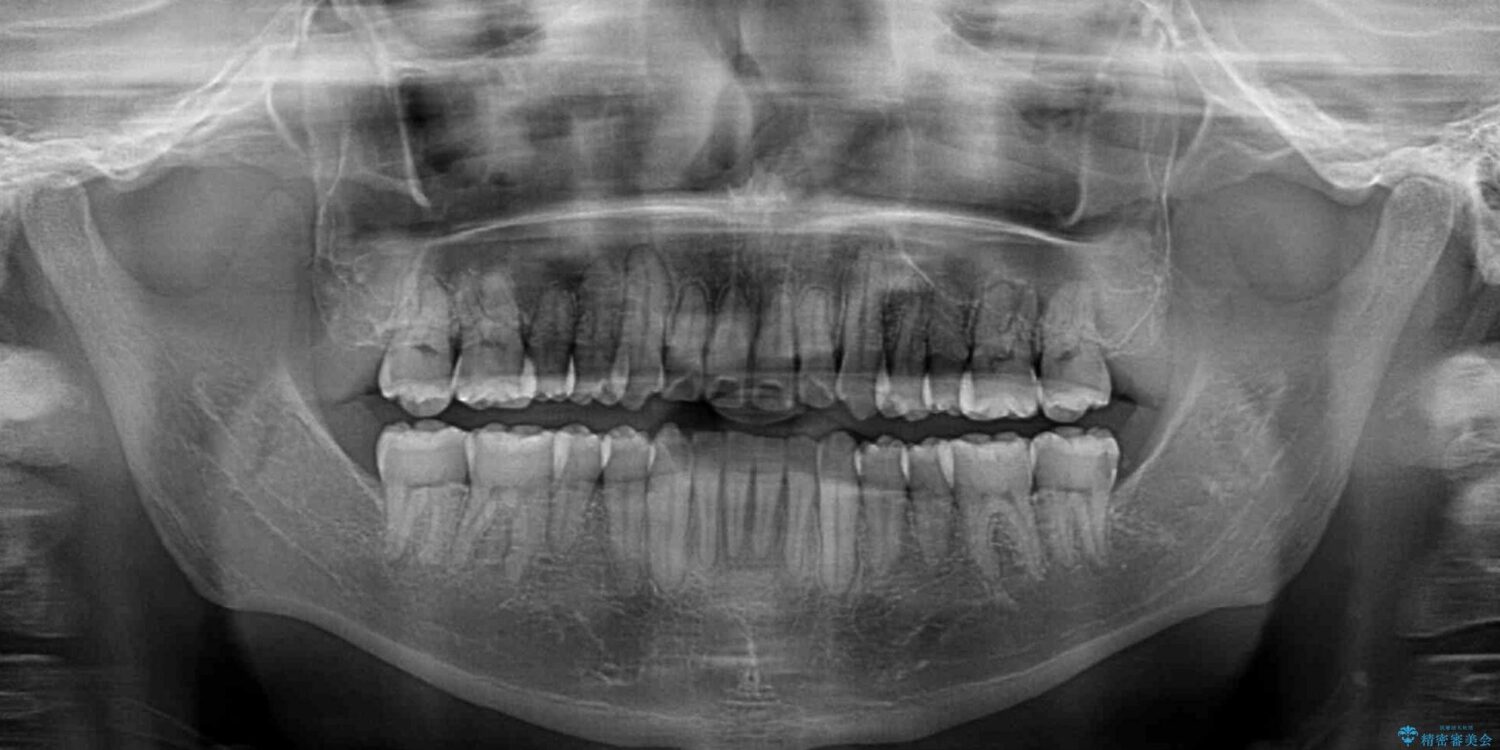

八重歯と前歯のクロスバイトを改善したいとのことで来院された患者様です。

デコボコの程度は強かったのですが、口元の突出感はなかったため、非抜歯矯正としました。

治療前

• 八重歯とクロスバイト 目立たないワイヤー装置で矯正治療 治療前画像